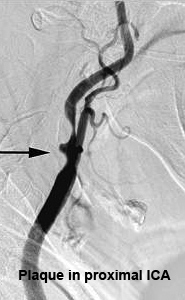

Carotid Arteriography

Conventional intra-arterial digital subtraction angiography has been considered the gold standard for imaging the cerebrovascular system. However, the risks of disabling cerebral infarction, systemic complications, and high cost make it less than ideal for screening and follow-up. In patients with arteriosclerosis, reports have found arteriography to be associated with a 4% risk of transient ischemic attack or minor cerebral infarction, a 1% risk of major cerebral infarction, and a <1% risk of mortality.[26] In patients with OIS, who have poor collateral circulation and severe carotid artery disease, arteriography-related risks may be even higher (Figure 11).